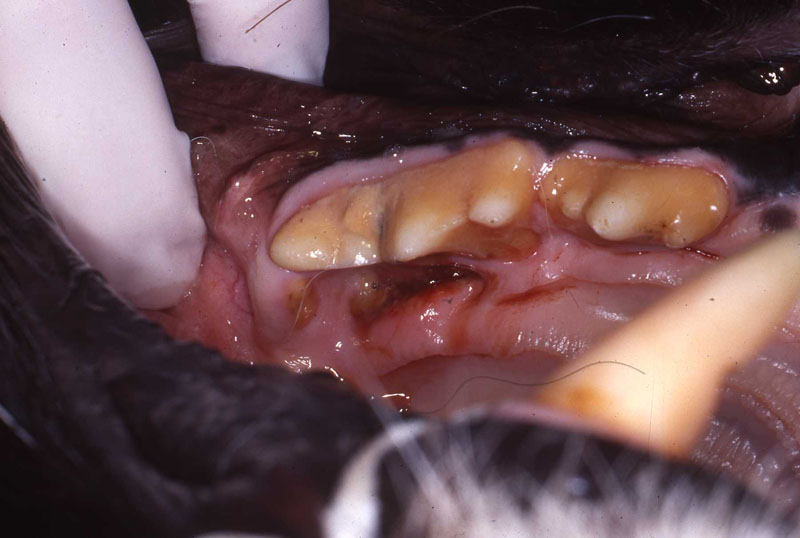

Feline Odontoclastic Resorptive Lesions

Felines exhibit a unique erosion at the cervical area called Feline Odontic Resorptive Lesions. These lesions appear to be associated with localized gingivitis. Many people have tried to explain why these lesions develop, however no one has come up with a definitive etiology.

I have restored FORL lesions with silver amalgam with excellent long term effect in multiple feline species. The lesions have ceased to enlarge. Restoration attempts with composite resin will fail, erosion will continue. Regrettably, most dentists and veterinary dentists will no longer have silver amalgam and the necessary instruments available to use it.

In personal conversations with Dr. Thomas Clark at Louisville Zoo I learned that he also has had success with silver amalgam. The lesion must be prepared with inverted cone burs to establish mechanical retention. These restorations have held up without failure for many years, see photos.